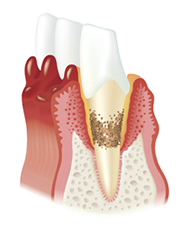

はじめは歯茎だけが腫れる歯肉炎に、そしてこの状態のまま放置すると、歯を支える歯槽骨が溶けてしまう歯周炎へと進行します。歯茎から血や膿が出たり、歯がぐらついて噛みにくく、口臭もひどくなっていきます。

歯周病はこうして進行します

-

歯と歯茎の間に

歯垢がたまります -

歯茎が赤くなり

腫れてきます -

歯槽骨が溶けて

後退してきます -

歯槽骨で歯を

支えられなくなります

健康な状態

歯周病にかかった状態

歯周病の進行

歯肉炎〜軽度の歯周炎

歯と歯ぐきの間にプラークがたまって歯ぐきが腫れ、出血しやすくなっています。歯を支える骨にはまだあまり影響がありません。

中度歯周炎

歯周ポケットが形成され、歯石が深部まで付着し、歯を支える骨を半分くらい失っています。

歯肉炎〜軽度の歯周炎

歯を支える骨がなくなってきて歯がぐらつき、このまま放っておくと歯が抜けてしまいます。歯ぐきが下がる、膿がでるなどの症状もみられます。